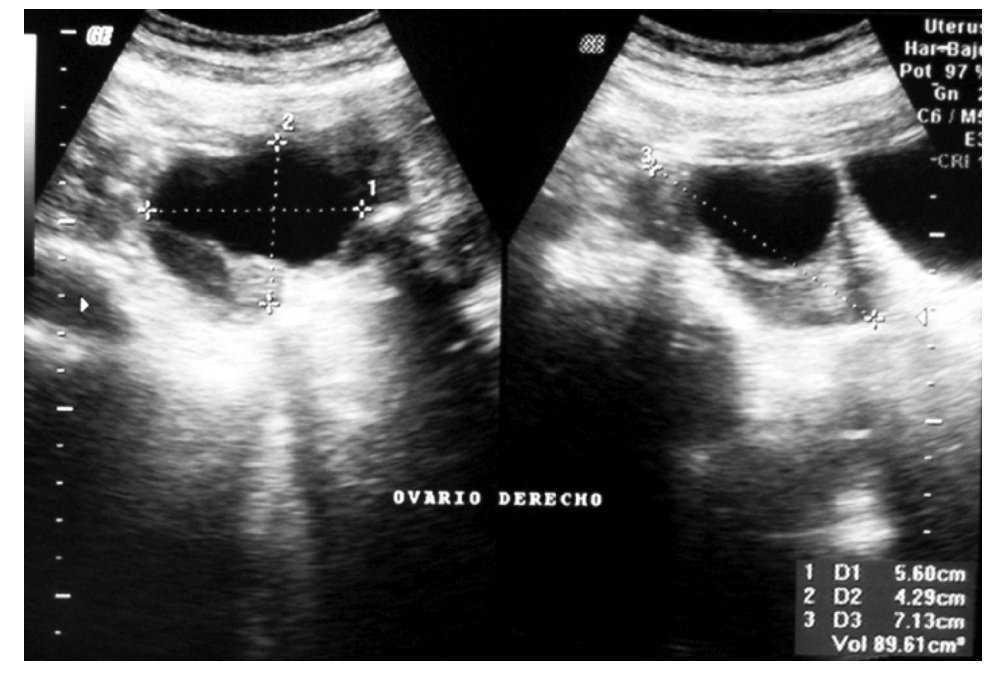

cobertura tallarines gorra Tumor pélvico asociado a incremento del CA125 por neoplasia benigna. Presentación de un caso resuelto por vía laparoscópica | Gaceta Mexicana de Oncología

cobertura tallarines gorra Tumor pélvico asociado a incremento del CA125 por neoplasia benigna. Presentación de un caso resuelto por vía laparoscópica | Gaceta Mexicana de Oncología

Pase para saber Psicológico pueblo Marcadores tumorales en el diagnóstico de cáncer epitelial de ovario: caso de estudio Tumor markers in the diagnosis of epit